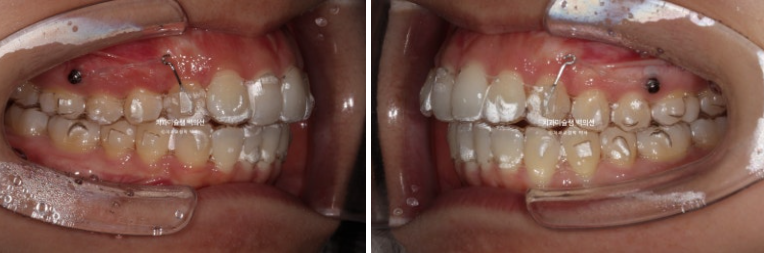

24년 7월까지 10개월간 42개 장치를 모두 낀 후 모습입니다.

24.07

중심선은 잘 맞지만

후방이동에 필요한 장치를 붙여놓았던 송곳니의 회전이 보입니다.

미진한 부분들을 정리하고자 추가장치 제작에 들어갑니다.